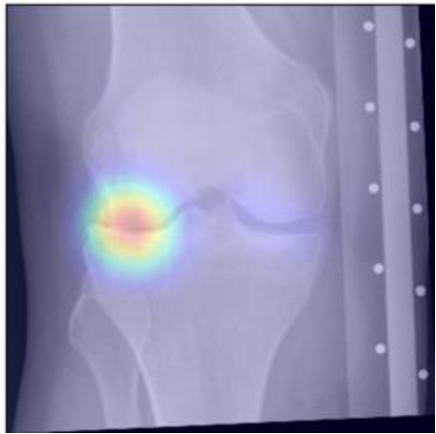

To gain insight into the basis of the CNN’s prediction, we used the GradCAM [24] approach and visualized the attention maps for the well-predicted knees. Examples of attention maps are presented in Figure 5. We observed that in various cases, the CNN paid attention to the compartment opposite to the one where degenerative change became visible during the follow-up visits. Additional examples of such attention maps are presented in Supplementary Figures 3, 4, 5 and 6.

Refer to caption

(a)

(b)

(c)

(d)

Figure 5: Examples of attention maps for progression cases and the corresponding visualization of progression derived using follow-up images from MOST datasets. Here, subplots (a) and (c) show the attention maps derived using a GradCAM approach. Subplots (b) and (d) show the joint-space areas from all the follow-up images (baseline to 84 months). Here, the subplot (b) corresponds to the attention map a) and the subplot (d) corresponds to the attention map (c).